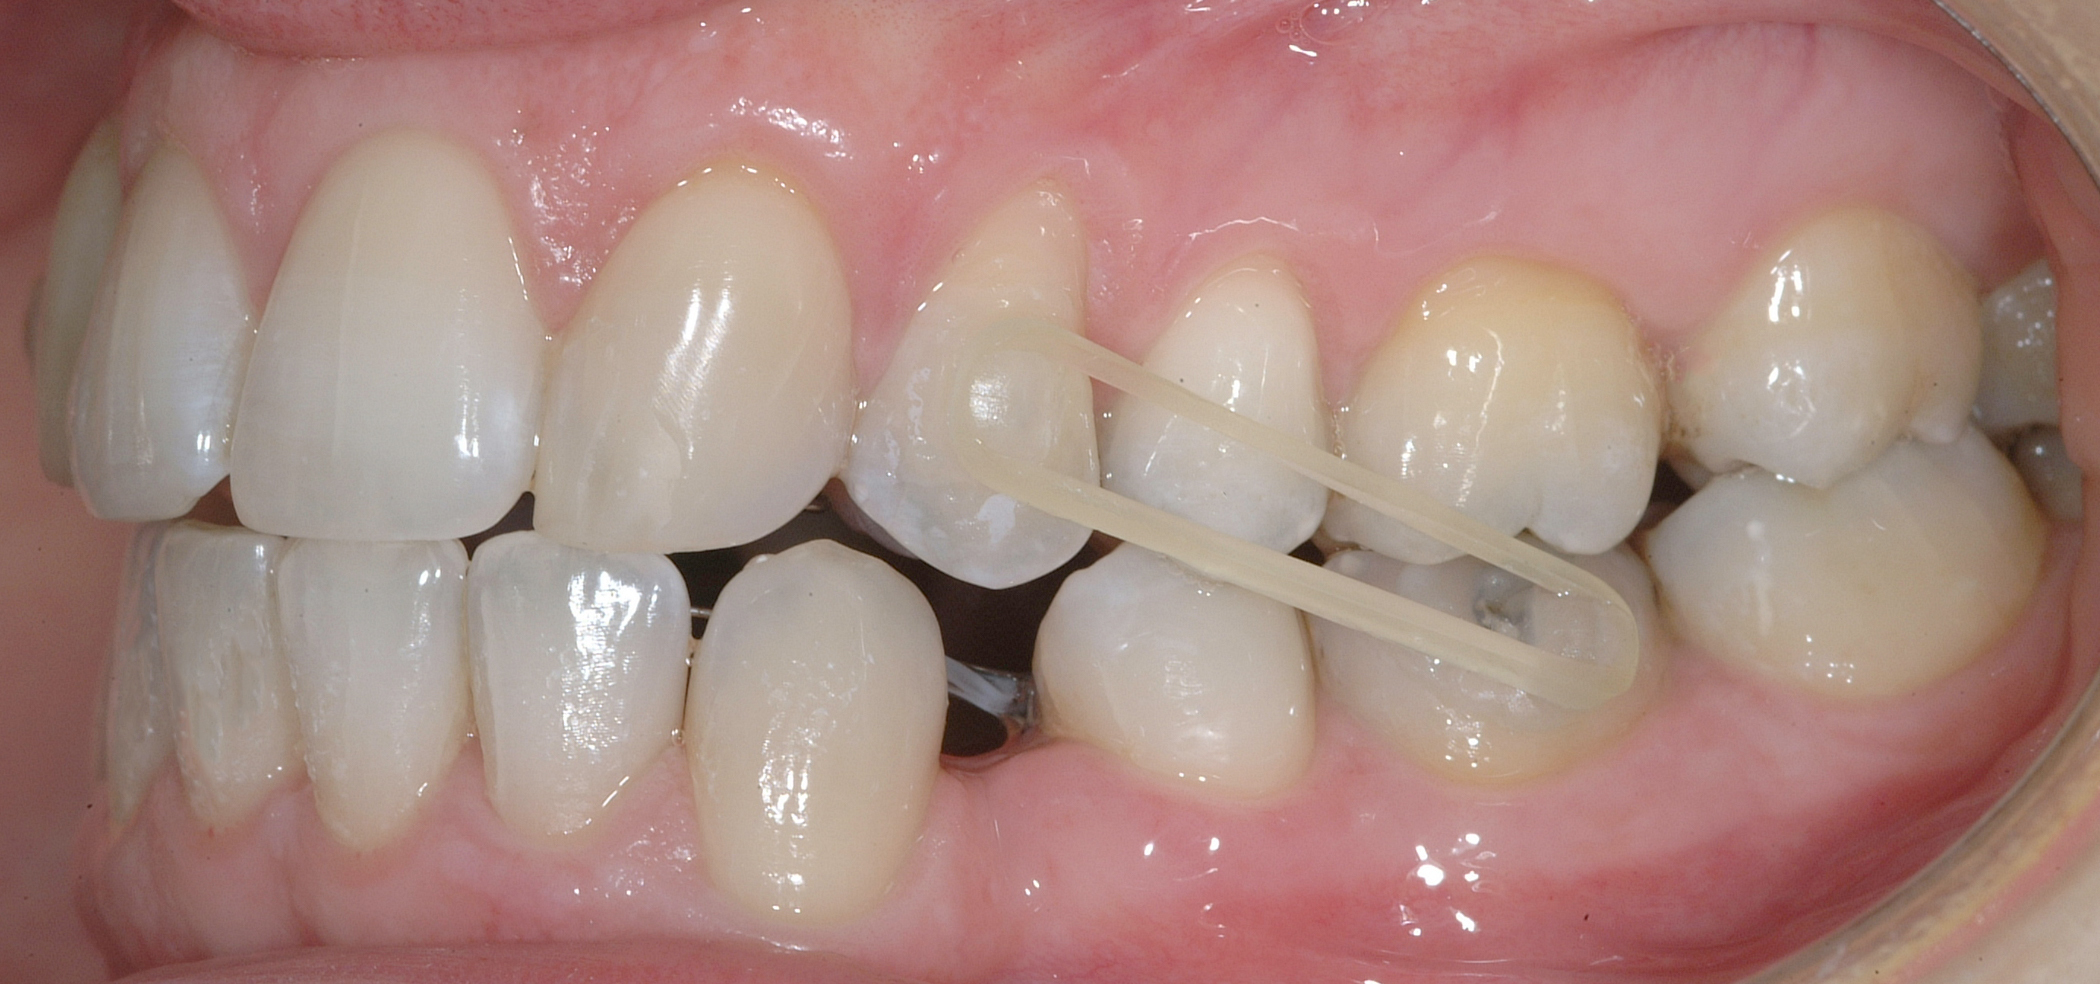

Il protocollo terapeutico ha previsto l’estrazione del primo premolare inferiore sinistro (3.4) e del primo superiore destro (1.4), l’applicazione di una apparecchiatura fissa linguale 2D e di una meccanica asimmetrica di ancoraggio e movimento ortodontico a entrambe le arcate (Figure 3a-b).

Il trattamento è iniziato con l’estrazione dei due premolari in unica seduta in anestesia locale e l’applicazione simultanea, dopo una settimana, della apparecchiatura linguale inferiore e superiore, non essendoci problemi di overbite e potenziali interferenze in occlusione tra l’apparecchiatura superiore e i frontali inferiori. All’arcata superiore è stata effettuata una iniziale chiusura dello spazio estrattivo con forze molto leggere in ancoraggio medio su arco .014” Nichel-Titanio e successivamente .016” Nichel-Titanio, bondato in prima fase per maggior stabilità direttamente sulla superficie mesiale di 2.4.

In seguito, è stato modellato e applicato con tecnica adesiva diretta un pontic estetico in resina composita in sede 1.2, bondato sia distalmente a 1.1 sia mesialmente a 1.3, per un movimento en-masse in ancoraggio medio del gruppo frontale superiore, ottenuto nel settore 1 mediante forza elastica singola su arco .016” acciaio.

Per completare la chiusura degli spazi inferiori in ancoraggio medio è stata applicata una catenella elastica leggera da 3 a 6 ed elastici di Classe II (3/16 da 4.5 once) bilaterali e domiciliari-notturni, applicati vestibolarmente su bottoni estetici bondati su 3.6, 4.6, 1.3 e 2.4 (Figure 7a-e).